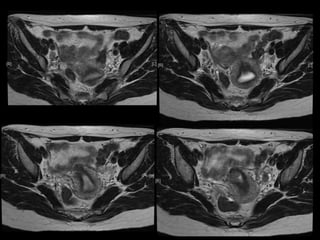

Dr. Hedvig Hricak

HISTORY

•   42 yo female

•   Recent immigrant from China

•   C/O postcoital and intermenstrual bleeding

•   Abnormal GYN exam

•   Abnormal biopsy

•   Further imaging performed

• What is the diagnosis?

• Staging?